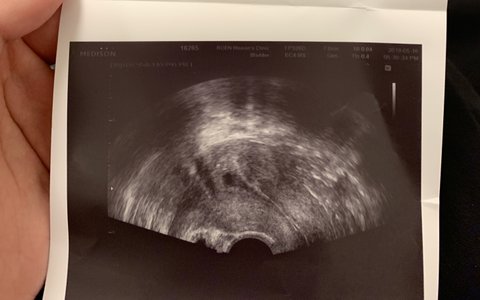

임테기는 비임신인데 병원 초음파에는 아기집

이거 정말 아기집 맞나요?